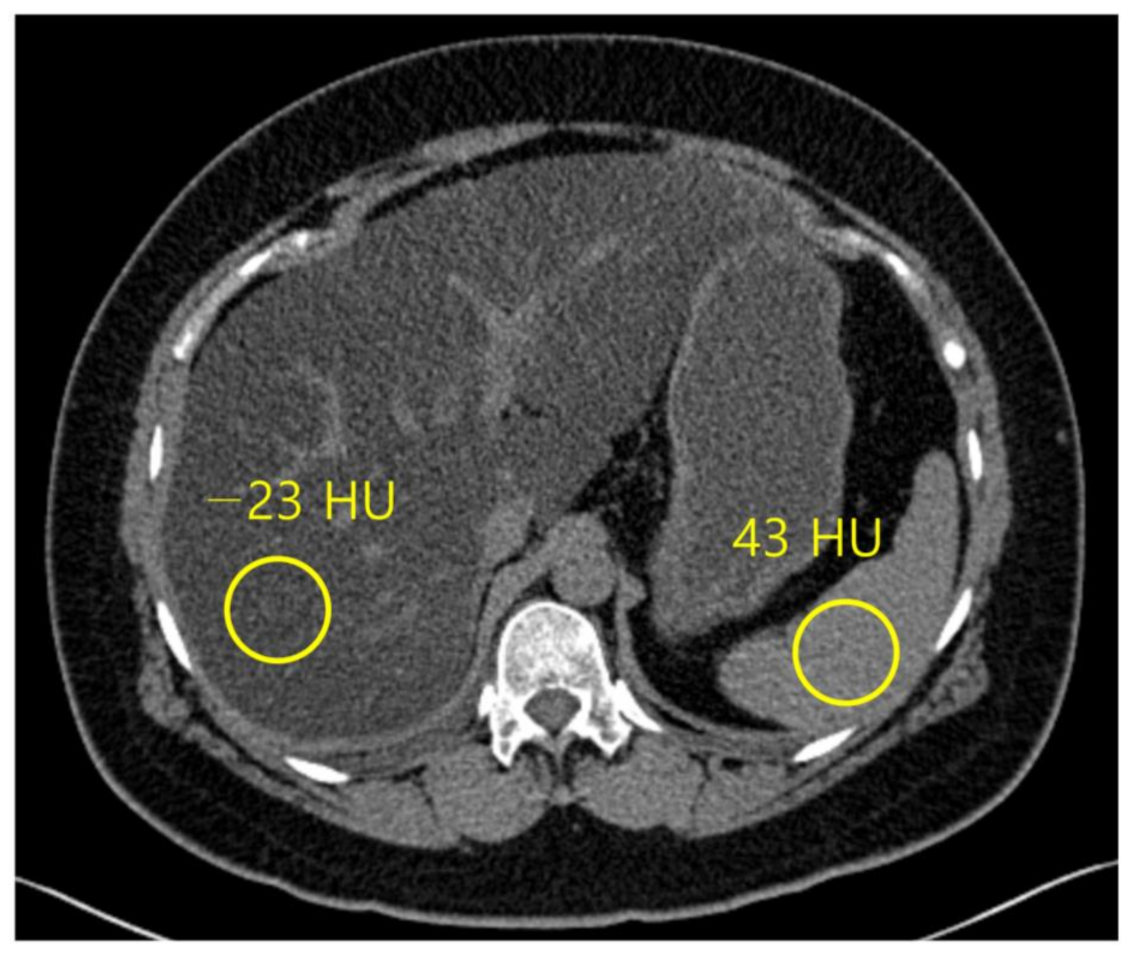

3.1. Conventional Unenhanced CT

Normal liver parenchyma is about 60 HU in unenhanced CT, and it hyperattenuates relative to the spleen [54], while steatosis is approximately at 40 HU, and the liver tissue hypoattenuates relative to the fat-free spleen [55] (Figure 4). The sensitivity and specificity of unenhanced CT for low-grade steatosis (cut-off values, 10–20%) are 57% and 88%, respectively. For high-grade steatosis (cut-off values, 25%), the sensitivity and specificity increase to 72% and 95%, respectively [21]. A HU threshold of 48 in unenhanced CT acquired at 120 kVp has been demonstrated to be strongly specific (100%) for high-grade steatosis (~30%), with a positive predictive value of 100%, negative predictive value of 94%, and a sensitivity of 54% [56].

Figure 4.

Non-contrast computed tomography shows the attenuation of the liver and spleen. The mean attenuation of the liver (−23 HU) is remarkably lower than the mean attenuation of the spleen (43 HU), which represents severe hepatic steatosis.